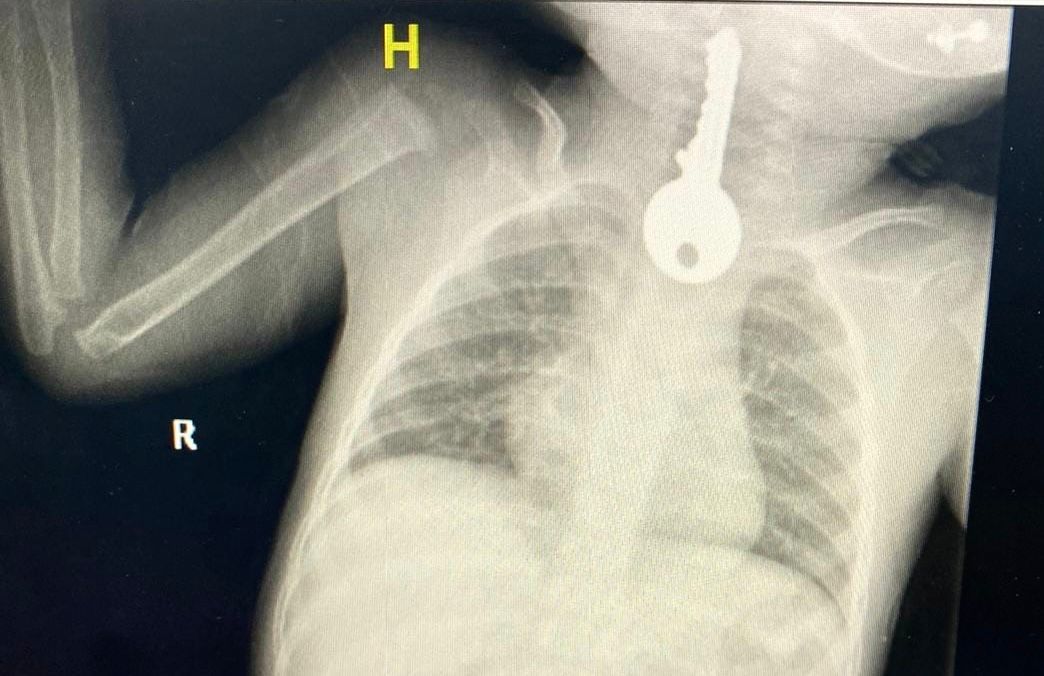

وبين مجمع الملك فيصل الطبي أنهم استقبلوا حالة طفل في وضع صحيحرج يعاني من ضيق في التنفس مما استدعى إلى تقديم الإسعافاتالأولية وإجراء الفحوصات السريرية والإشعاعية التي كشفت وجود جسمغريب على شكل مفتاح في المريء.

وقال الفريق المعالج للحالة أنه تم على الفور عمل منظار عاجل واستخراجمفتاح حديدي من المريء كاد أن يودي بحياته ثم متابعته في قسم التنويممن قبل الفرق التمريضية حتى استقرت الحالة وخرج بالسلامة وللهالحمد.